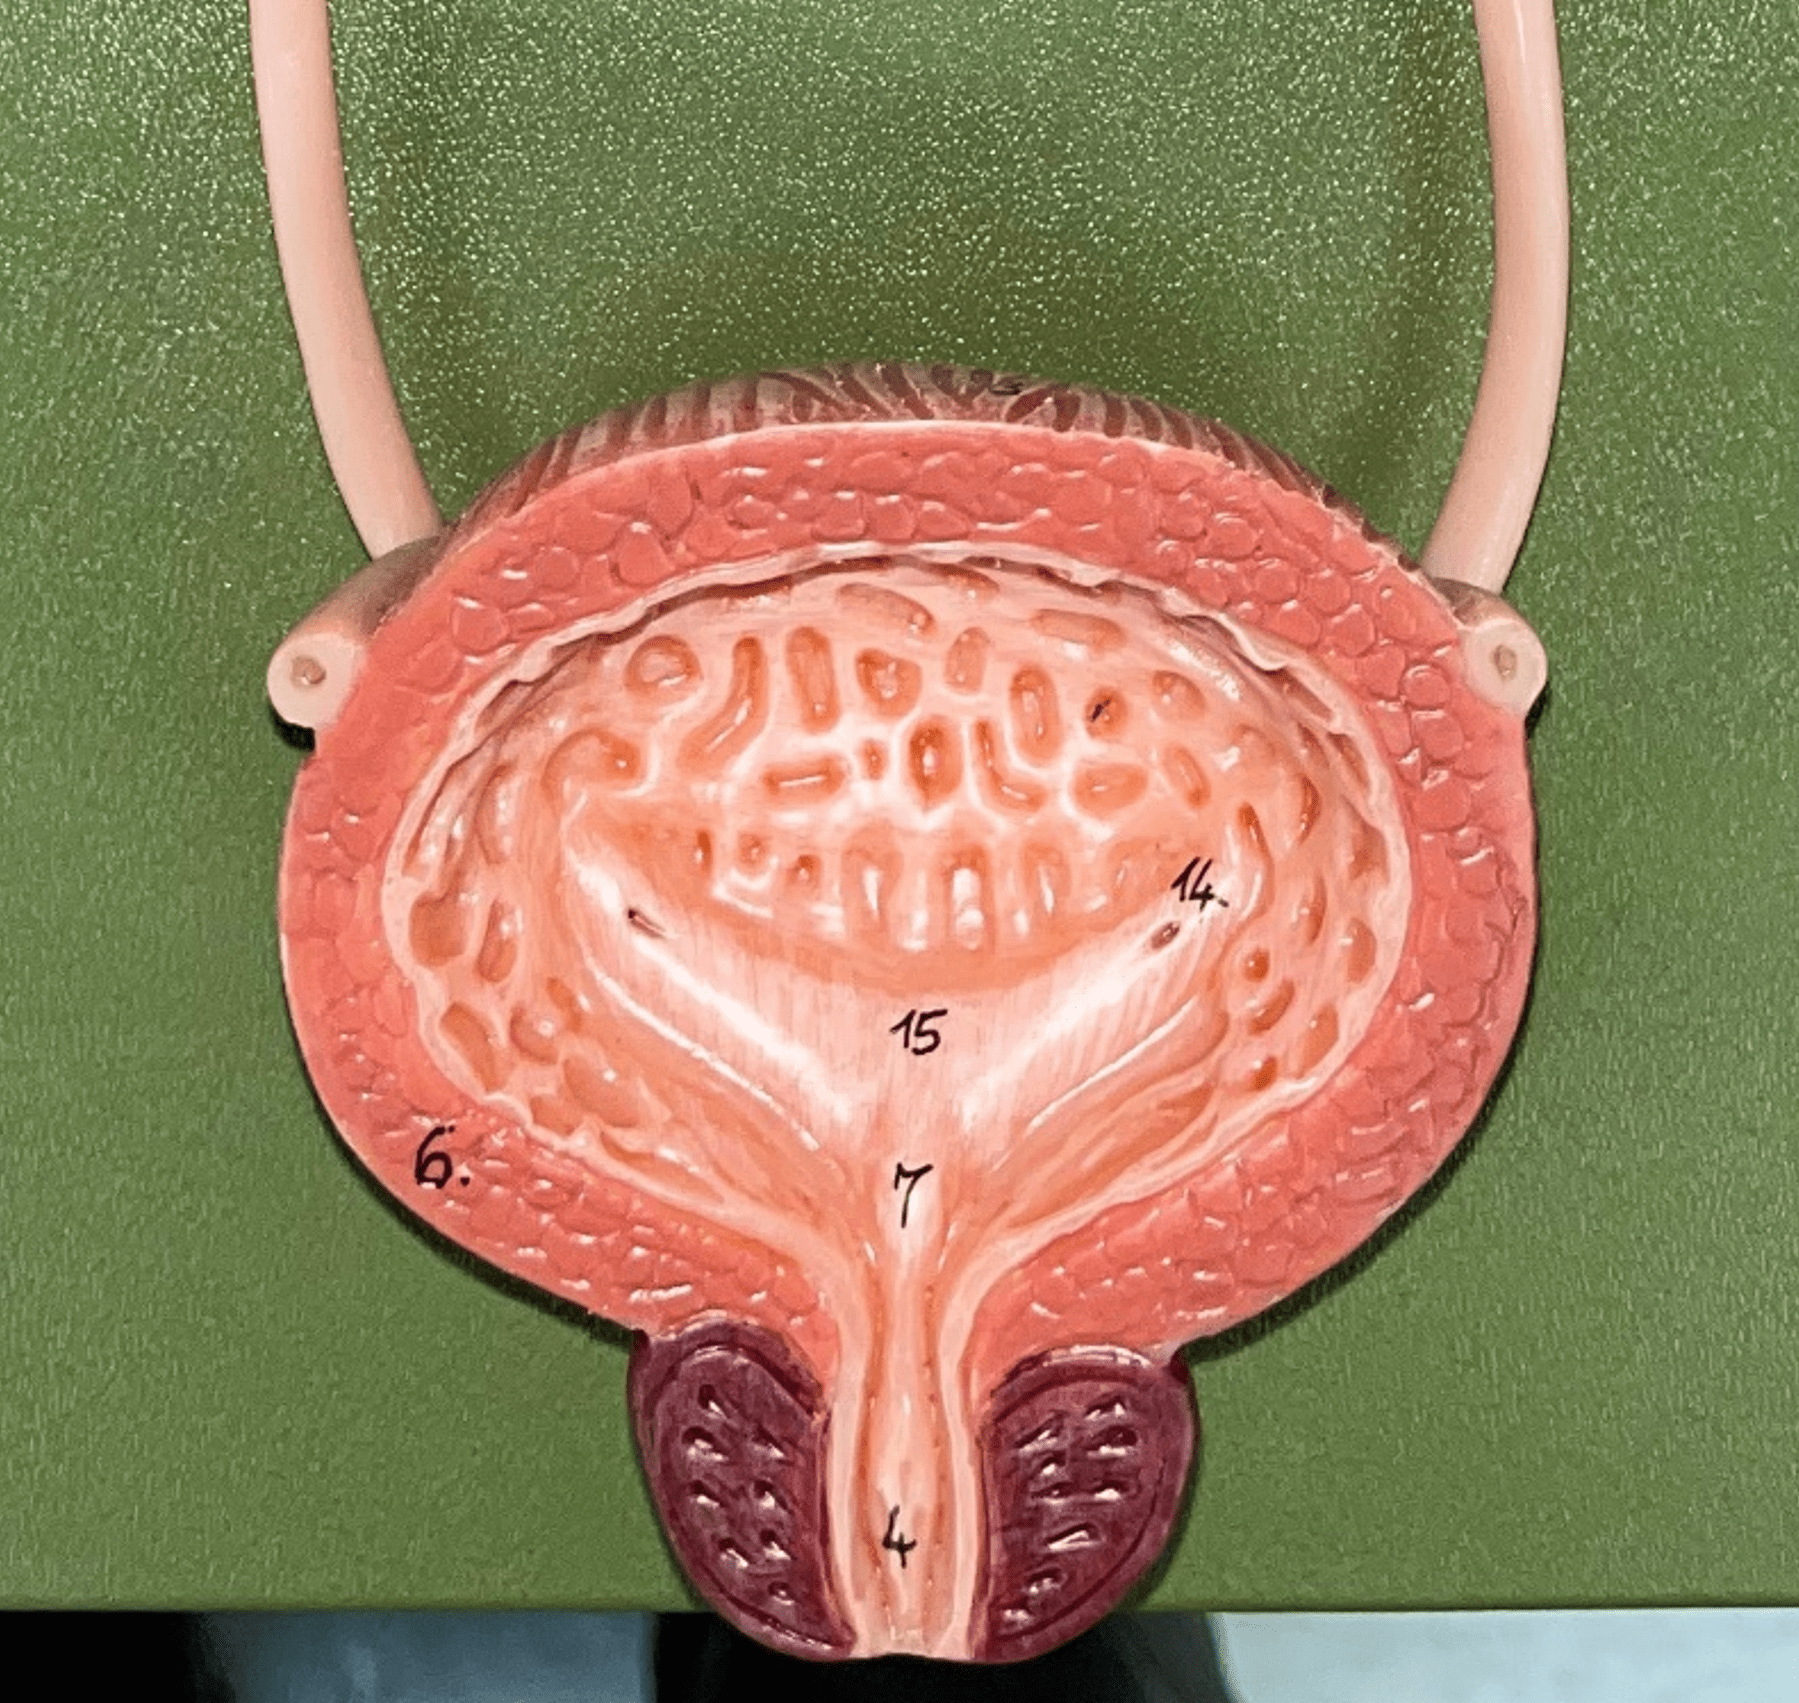

urinary bladder

The hollow sac organ that collects and temporarily stores urine.

27

New cards

rugae

• Part of the urinary bladder.

• Folds of the mucous membrane of the bladder.

• Flattens as the bladder fills with urine to increase capacity.

• Folds of the mucous membrane of the bladder.

• Flattens as the bladder fills with urine to increase capacity.

28

New cards

trigone

• Part of the urinary bladder.

• The triangle formed by the ureteral openings and internal urethra orifice.

• The triangle formed by the ureteral openings and internal urethra orifice.

29

New cards

ureteral opening

• Part of the urinary bladder.

• A posterior opening on either side of the of the bladder led in by the ureters.

• A posterior opening on either side of the of the bladder led in by the ureters.

30

New cards

internal urethral orifice

• Part of the urinary bladder.

• The anterior opening of the bladder leading to the urethra.

• The anterior opening of the bladder leading to the urethra.

31

New cards

detrusor muscle

• Part of the urinary bladder.

• The muscularis of the bladder.

• Contracts to expel urine from the bladder.

• The muscularis of the bladder.

• Contracts to expel urine from the bladder.

32